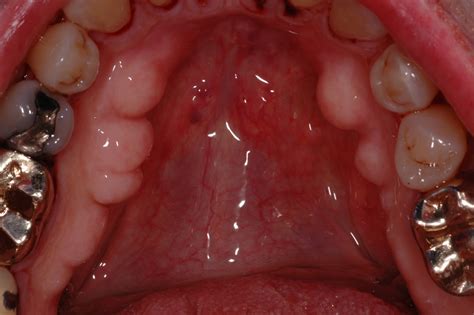

• Torus Palatinus: These occur on the hard palate, which is the roof of the mouth. They often appear as a singular or lobulated bony mass located in the center of the palate.

• Torus Mandibularis: These appear on the lingual aspect of the mandible, which is the inner side of your lower jaw, usually located near the premolar teeth. They are often bilateral, meaning they appear on both the left and right sides of the jaw.